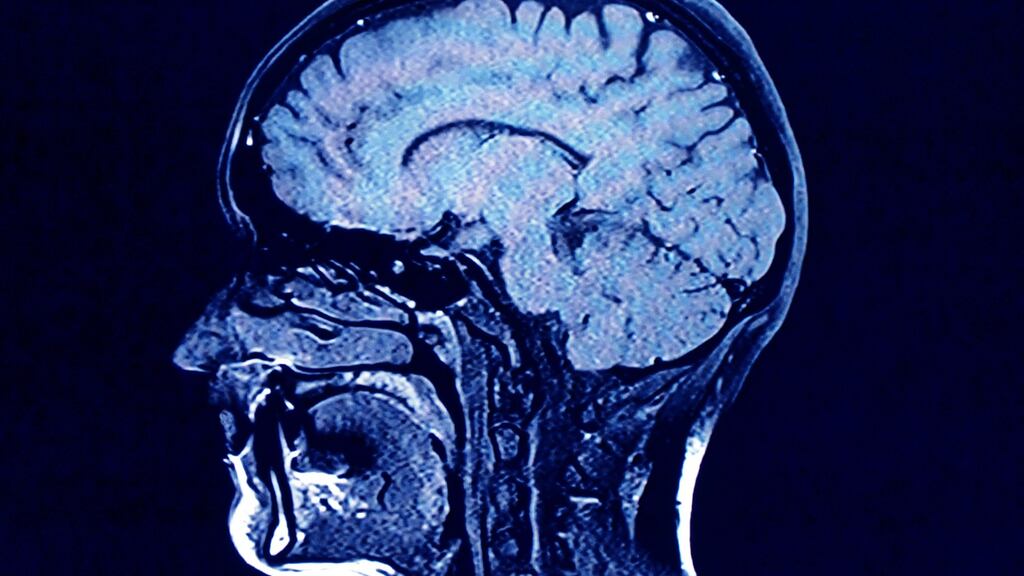

Dr Doherty will reveal evidence showing abnormalities in brain function from the tested players, in some cases two hours after playing a rugby match.

“The point is, and our hypothesis is, this leakiness is happening even in minor sub-concussive blows. In order to see it you need a very sophisticated set of examinations.”